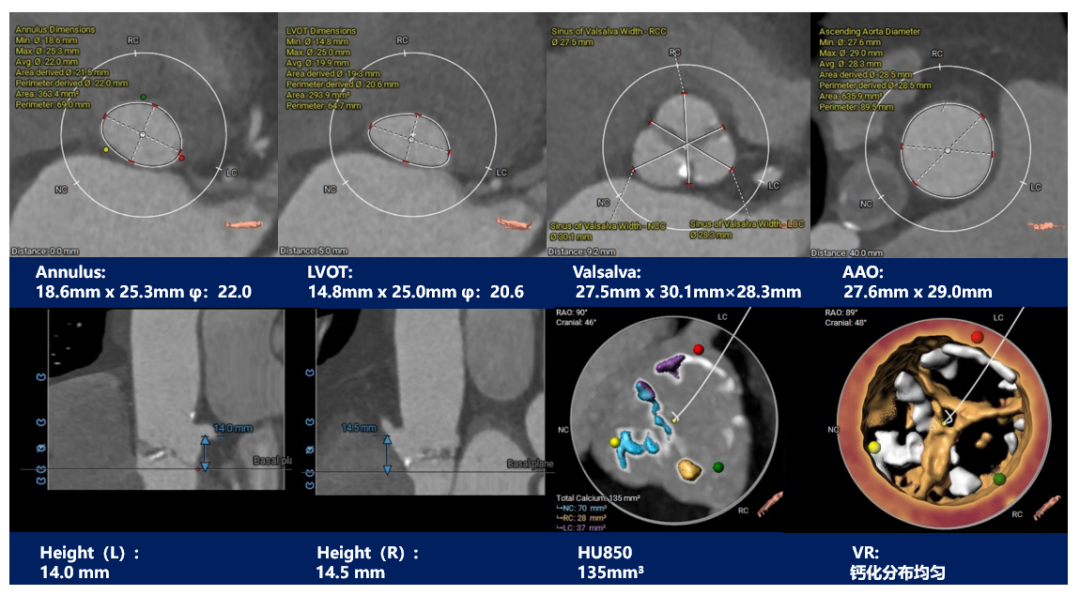

主动脉根部测量:

三叶式主动脉瓣,窦部发育均匀,瓣叶中重度钙化并纤维增厚,钙化分布相对均匀,主要分布在瓣叶边缘及管壁附着缘 ,右冠开口高度可,左冠开口高度偏低为8.8mm,左右冠脉切线位瓣叶长度>冠脉开口到瓣叶根部附着缘距离;冠脉可见钙化斑块。

瓣环上解剖结构评估:

主动脉根部评估:

三叶式主动脉瓣,中度钙化并瓣叶增生肥厚,钙化分布欠均匀,主要分布在瓣叶边缘及血管壁附着缘-左右冠高度可,冠脉切线位瓣叶长度<冠脉开口到瓣叶根部附着缘距离;冠脉可见散在钙化-流入端呈收口,瓦氏窦、STJ及升主动脉内径偏小。

瓣上测量: